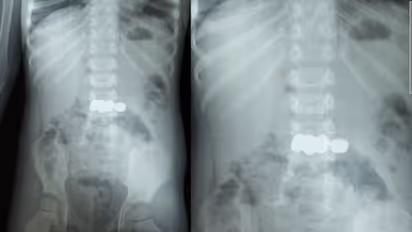

മേപ്പാടി: കളിക്കുന്നതിനിടെ അബദ്ധത്തിൽ അഞ്ച് ബാറ്ററികൾ വിഴുങ്ങിയ രണ്ട് വയസ്സുകാരന് ഡോ. മൂപ്പൻസ് മെഡിക്കൽ കോളേജിൽ നടത്തിയ അടിയന്തര എൻഡോസ്കോപ്പിയിലൂടെ പുനർജന്മം. ബത്തേരി മൂലങ്കാവ് സ്വദേശികളായ ദമ്പതികളുടെ മകനാണ് കളിപ്പാട്ടത്തിലെ ബാറ്ററികൾ വിഴുങ്ങിയത്. ഡോക്ടർമാരുടെ കൃത്യസമയത്തുള്ള ഇടപെടൽ മൂലം വലിയൊരു അപകടം ഒഴിവാക്കാനായി.

കുട്ടി ബാറ്ററികൾ വായിലിടുന്നത് ശ്രദ്ധയിൽപ്പെട്ട വീട്ടുകാർ ഒട്ടും വൈകാതെ തന്നെ കുട്ടിയെ മെഡിക്കൽ കോളേജിലെത്തിച്ചു. ഗാസ്ട്രോ എന്ററോളജി വിഭാഗം സ്പെഷ്യലിസ്റ്റ് ഡോ. സൂര്യനാരായണന്റെ നേതൃത്വത്തിലാണ് ബാറ്ററികൾ പുറത്തെടുക്കാനുള്ള നടപടികൾ ആരംഭിച്ചത്. എൻഡോസ്കോപ്പിയിലൂടെ അഞ്ച് ബാറ്ററികളും സുരക്ഷിതമായി പുറത്തെടുത്തു. ഡോ. അഖിൽ, ഡോ. അഞ്ജന എന്നിവരും ഈ ദൗത്യത്തിൽ പങ്കാളികളായി.

ബാറ്ററികൾ വിഴുങ്ങുന്നത് ജീവന് തന്നെ ഭീഷണിയാണെന്ന് ഡോക്ടർമാർ മുന്നറിയിപ്പ് നൽകുന്നു: വയറ്റിലെ അസിഡിക് പ്രവർത്തനം മൂലം ബാറ്ററികൾ പൊട്ടിപ്പോകാൻ സാധ്യതയുണ്ട്. ബാറ്ററി പൊട്ടിയാൽ പുറന്തള്ളപ്പെടുന്ന രാസവസ്തുക്കൾ കുടൽ, കരൾ തുടങ്ങിയ പ്രധാന അവയവങ്ങൾക്ക് ഗുരുതരമായ നാശമുണ്ടാക്കും. കൃത്യസമയത്ത് എൻഡോസ്കോപ്പിയിലൂടെ ഇവ പുറത്തെടുക്കാൻ സാധിച്ചില്ലെങ്കിൽ സങ്കീർണ്ണമായ ശസ്ത്രക്രിയകളിലേക്ക് നീങ്ങേണ്ടി വരുമായിരുന്നു.